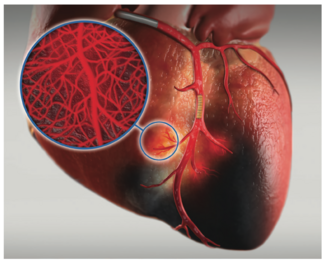

We have taken the step of treating not just the epicardial vessels, but also treating the microvasculature and addressing no-reflow with SuperSaturated Oxygen (SSO2) Therapy to reduce infarct size (TherOx SSO2 Therapy, ZOLL Medical).